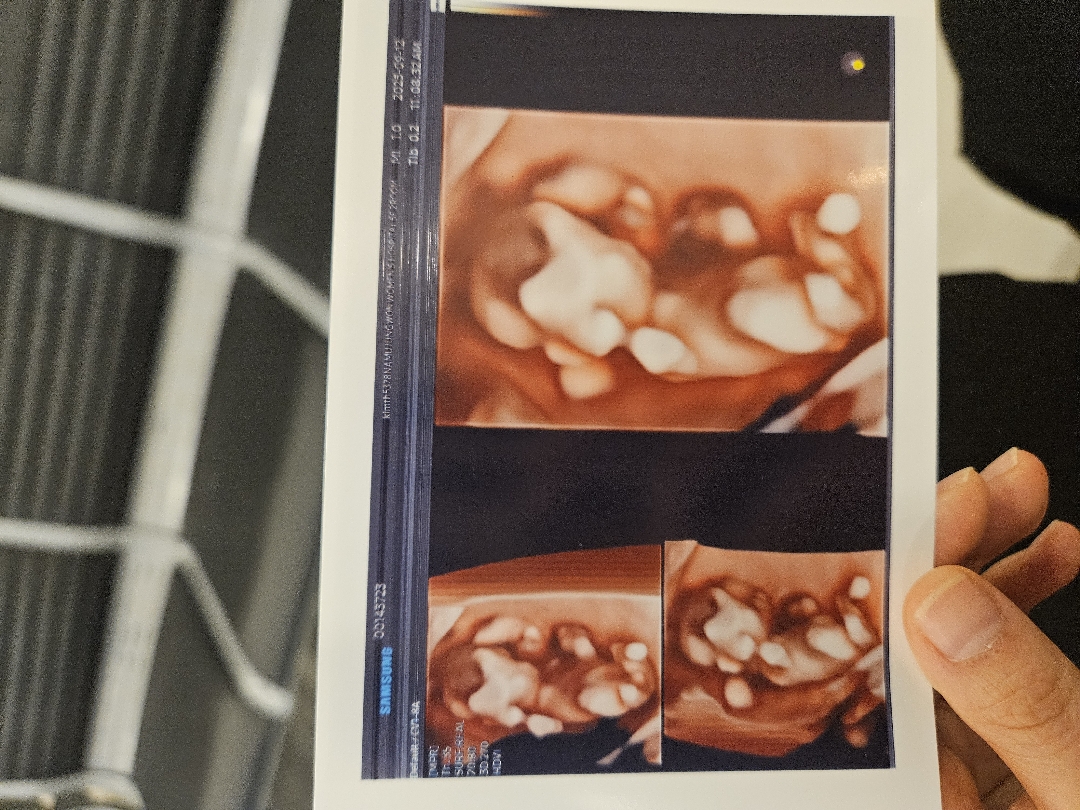

12주차 정밀초음파봤는데 아들인가요?

다리사이에 저게 고추...일까요? 딸들도 저렇게 보인다고 아니라고 하시는데 의사선생님은 ㅋㅋㅋ존재감이...